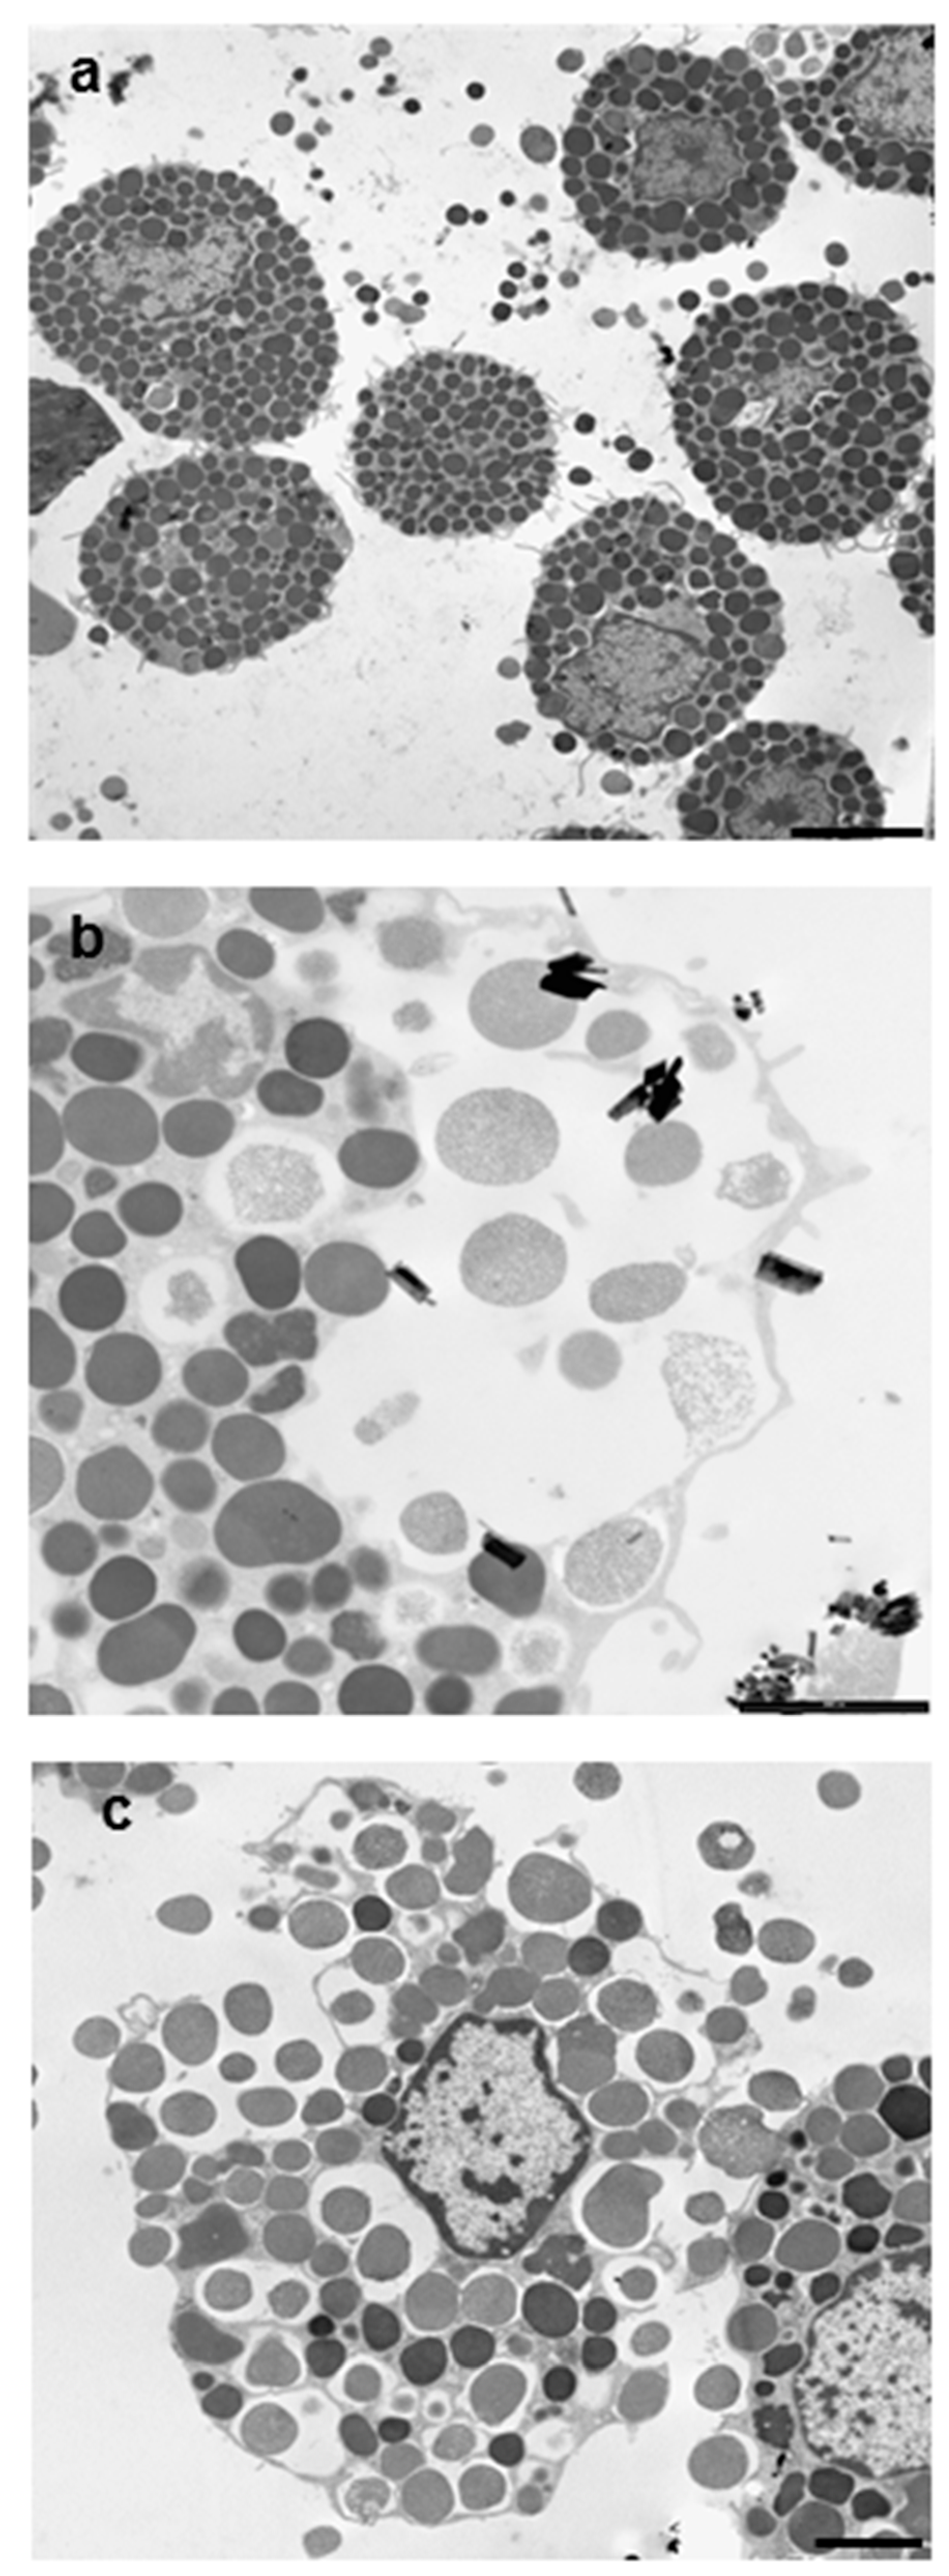

3.1. Morphological Analysis of Mineral Fiber–RPMC Interaction by Light and Electron Microscopy